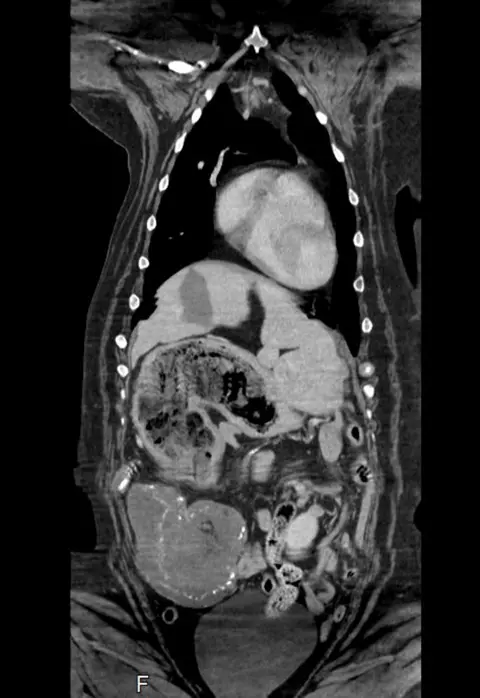

Eight-year-old Maisy had a CT scan which showed an unusually full stomach and a mass on her spleen, which led her vet to diagnose possible cancer.

During an operation to remove the spleen, Wakefield-based vet Nick Blackburn found the soft toys in her stomach.